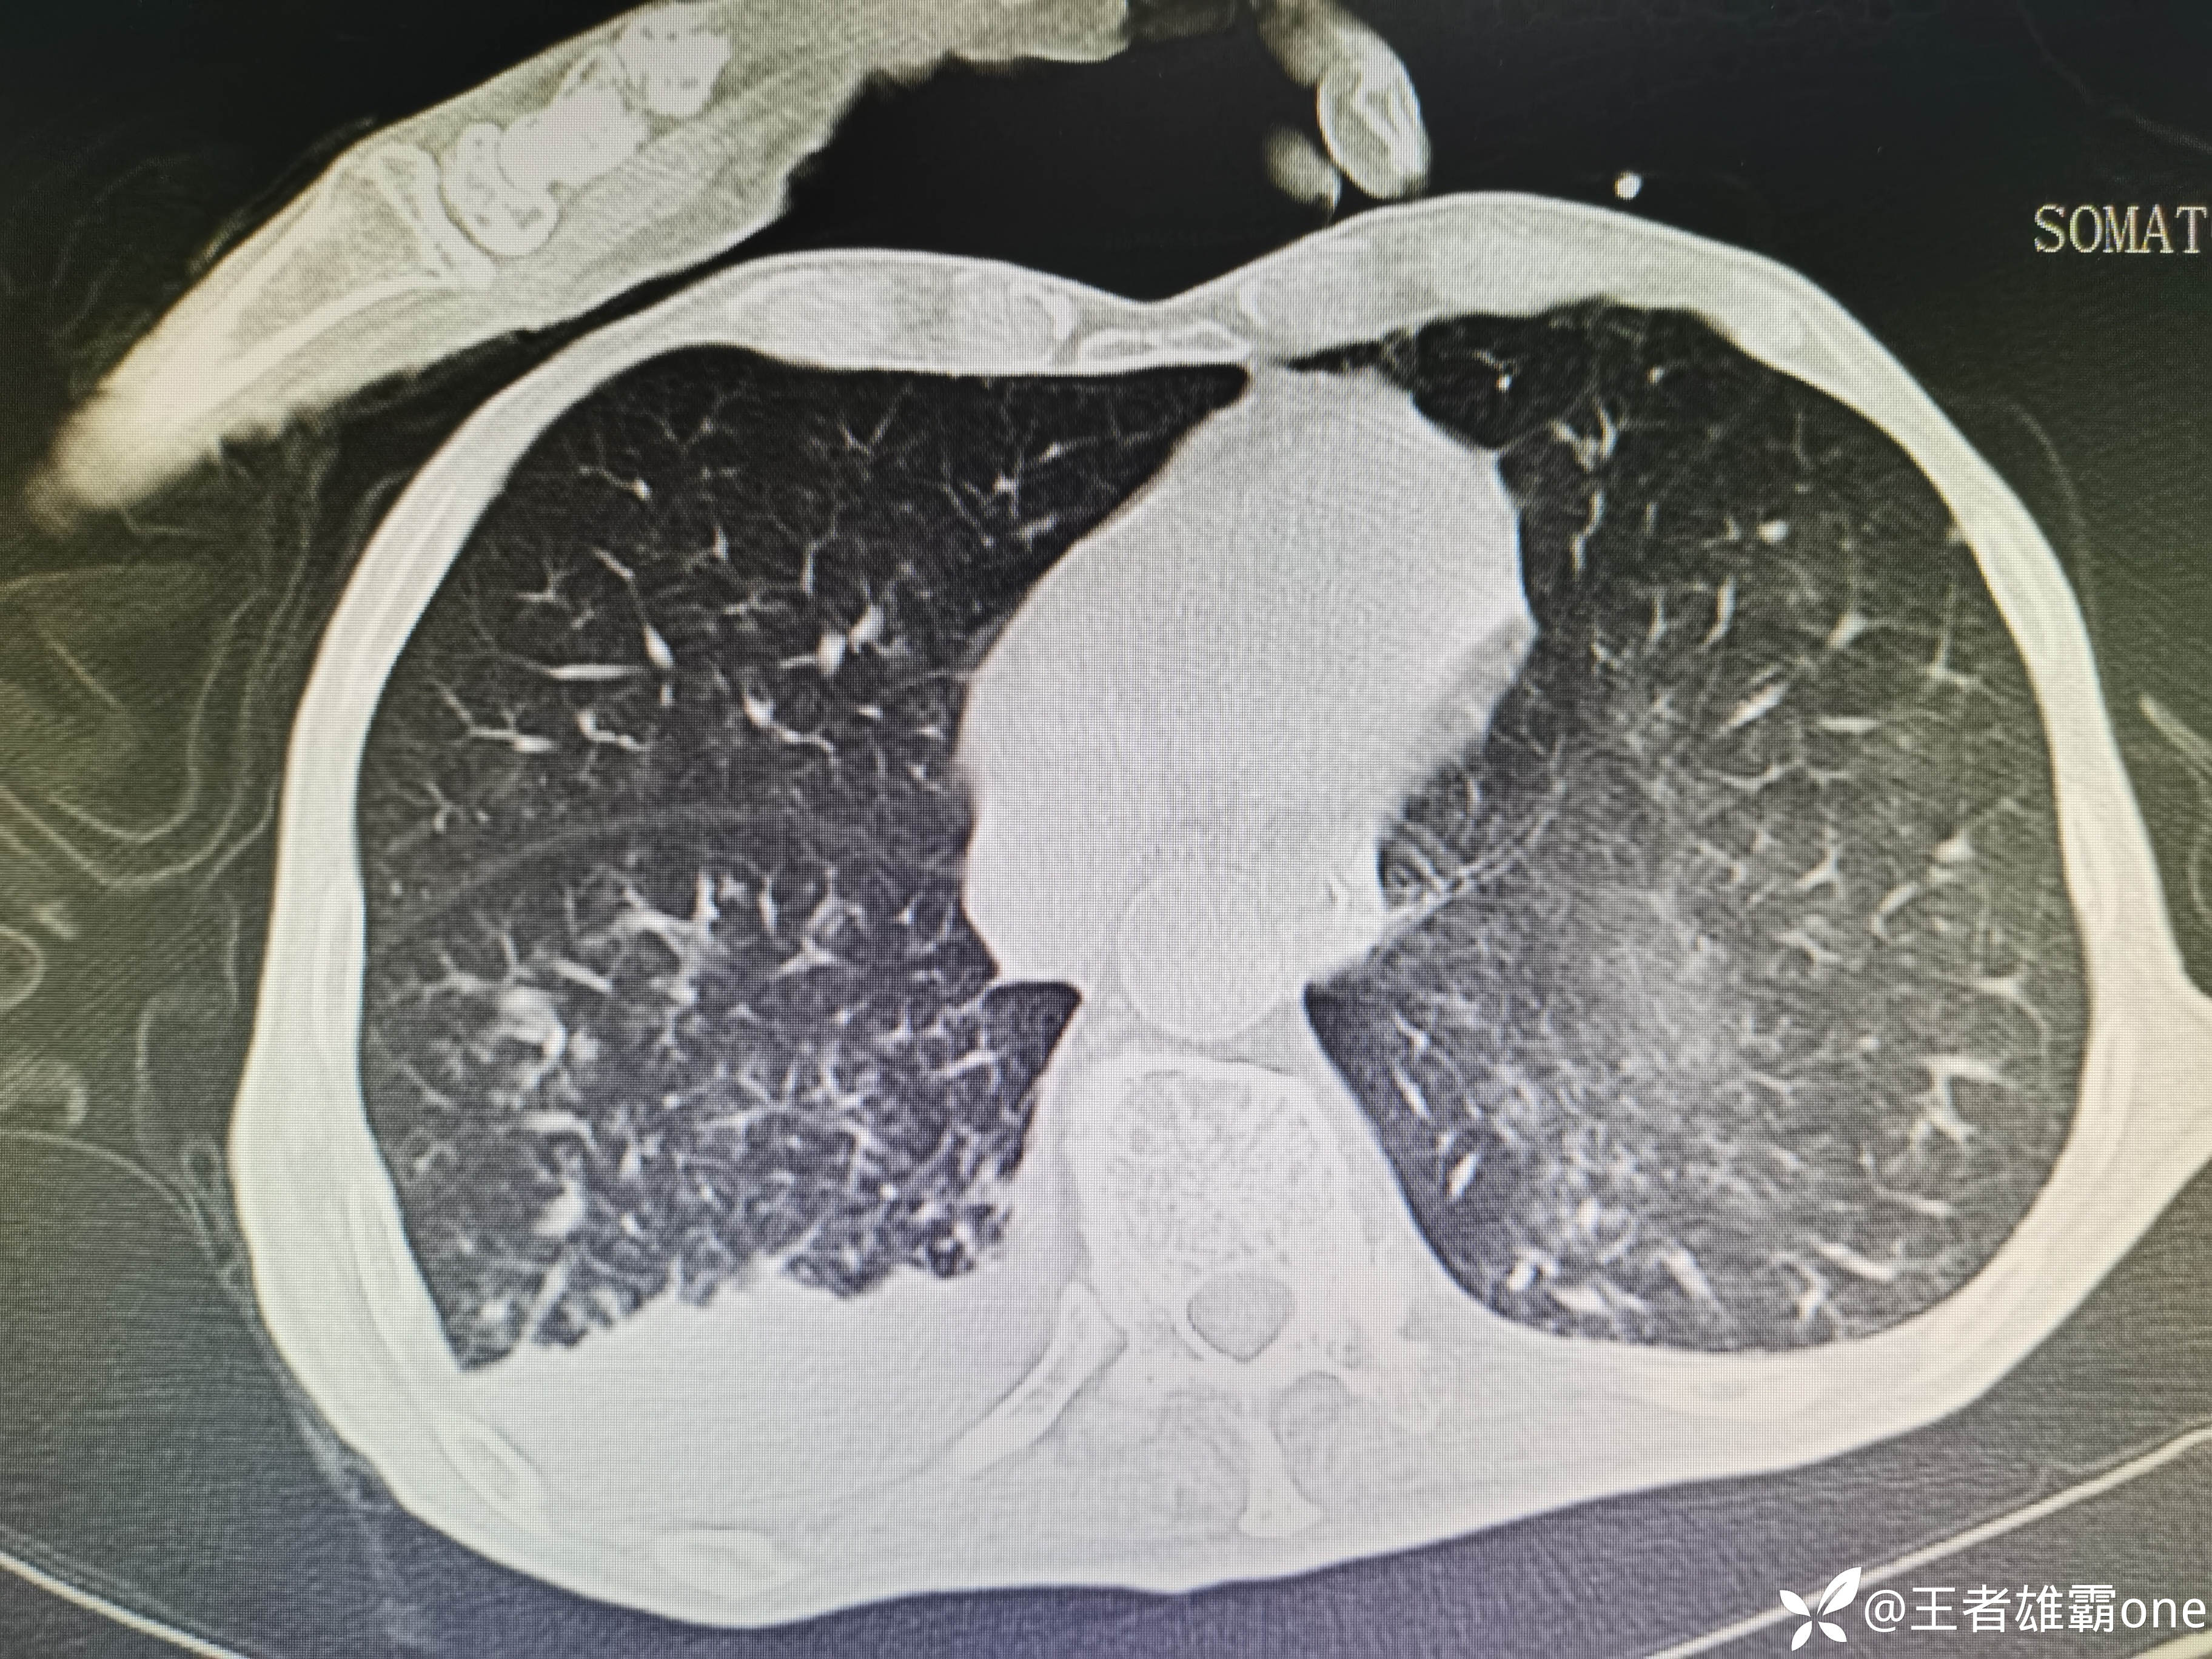

入院时胸部CT:

具体图片: